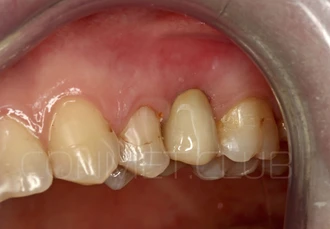

Через 8 недель проводится внутриротовое сканирование. Зафиксирован сканмаркер, который позволяет перенести данные сканирования в виде STL файла в программу ExoCad, осуществить моделирование индивидуального абатмента и выточить его на фрезерном станке.